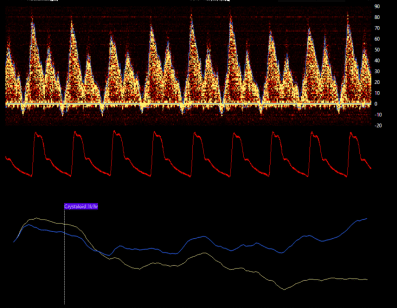

Echocardiography uses the Systolic/Diastolic wave ratios in ventricular performance assessment. The Nilus algorithm calculates the S/D ratio continuously and in real-time, providing a valuable parameter for the Right Heart performance.

The picture shows a healthy right heart pattern. During ventricular overload or failure, the pattern quickly changes. Most frequently, the S wave typically becomes less pronounced than the D wave.

Continuous monitoring adds significant value to the scheduled regular ultrasound examination, typically performed maximally a few times a day.